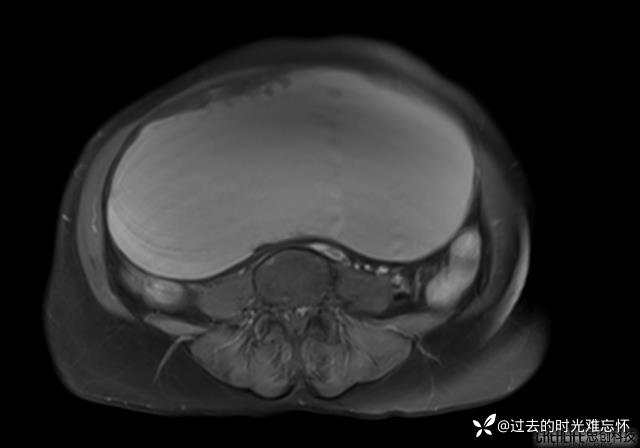

患者性别:女

患者年龄:65岁

主诉: 发现腹部隆起半年余。无其他明显不适。

浆液性囊腺瘤 (22)